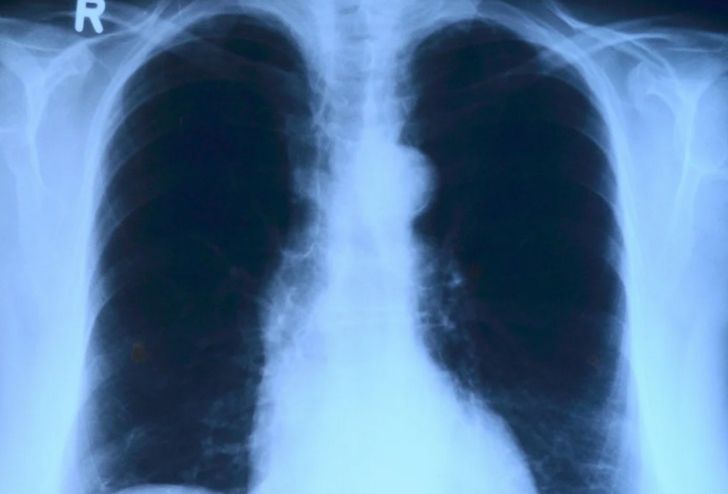

ХОБЛ характеризуется сужением дыхательных путей и считается болезнью курильщиков. При этом недуг нередко возникает и у людей, которые никогда не курили.

По словам исследователей из США, фактором развития хронической обструктивной болезни лёгких является не только курение, но и небольшой размер дыхательных путей относительно всего объёма органа.

В результате выяснилось, что несоответствие размеров дыхательных путей объёму лёгких увеличивает риск развития ХОБЛ и онкологического заболевания.